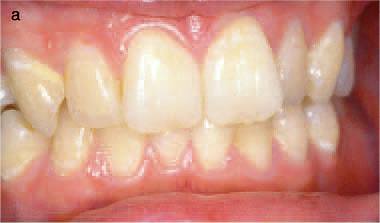

ตัวอย่างทางคลินิกของ Class 1 สังเกตซี่ 12 บริเวณขอบเหงือกที่มีลักษณะแดงและไม่เรียบ

film 12 แสดงรอยโรค Invasive cervical resorption Class 1